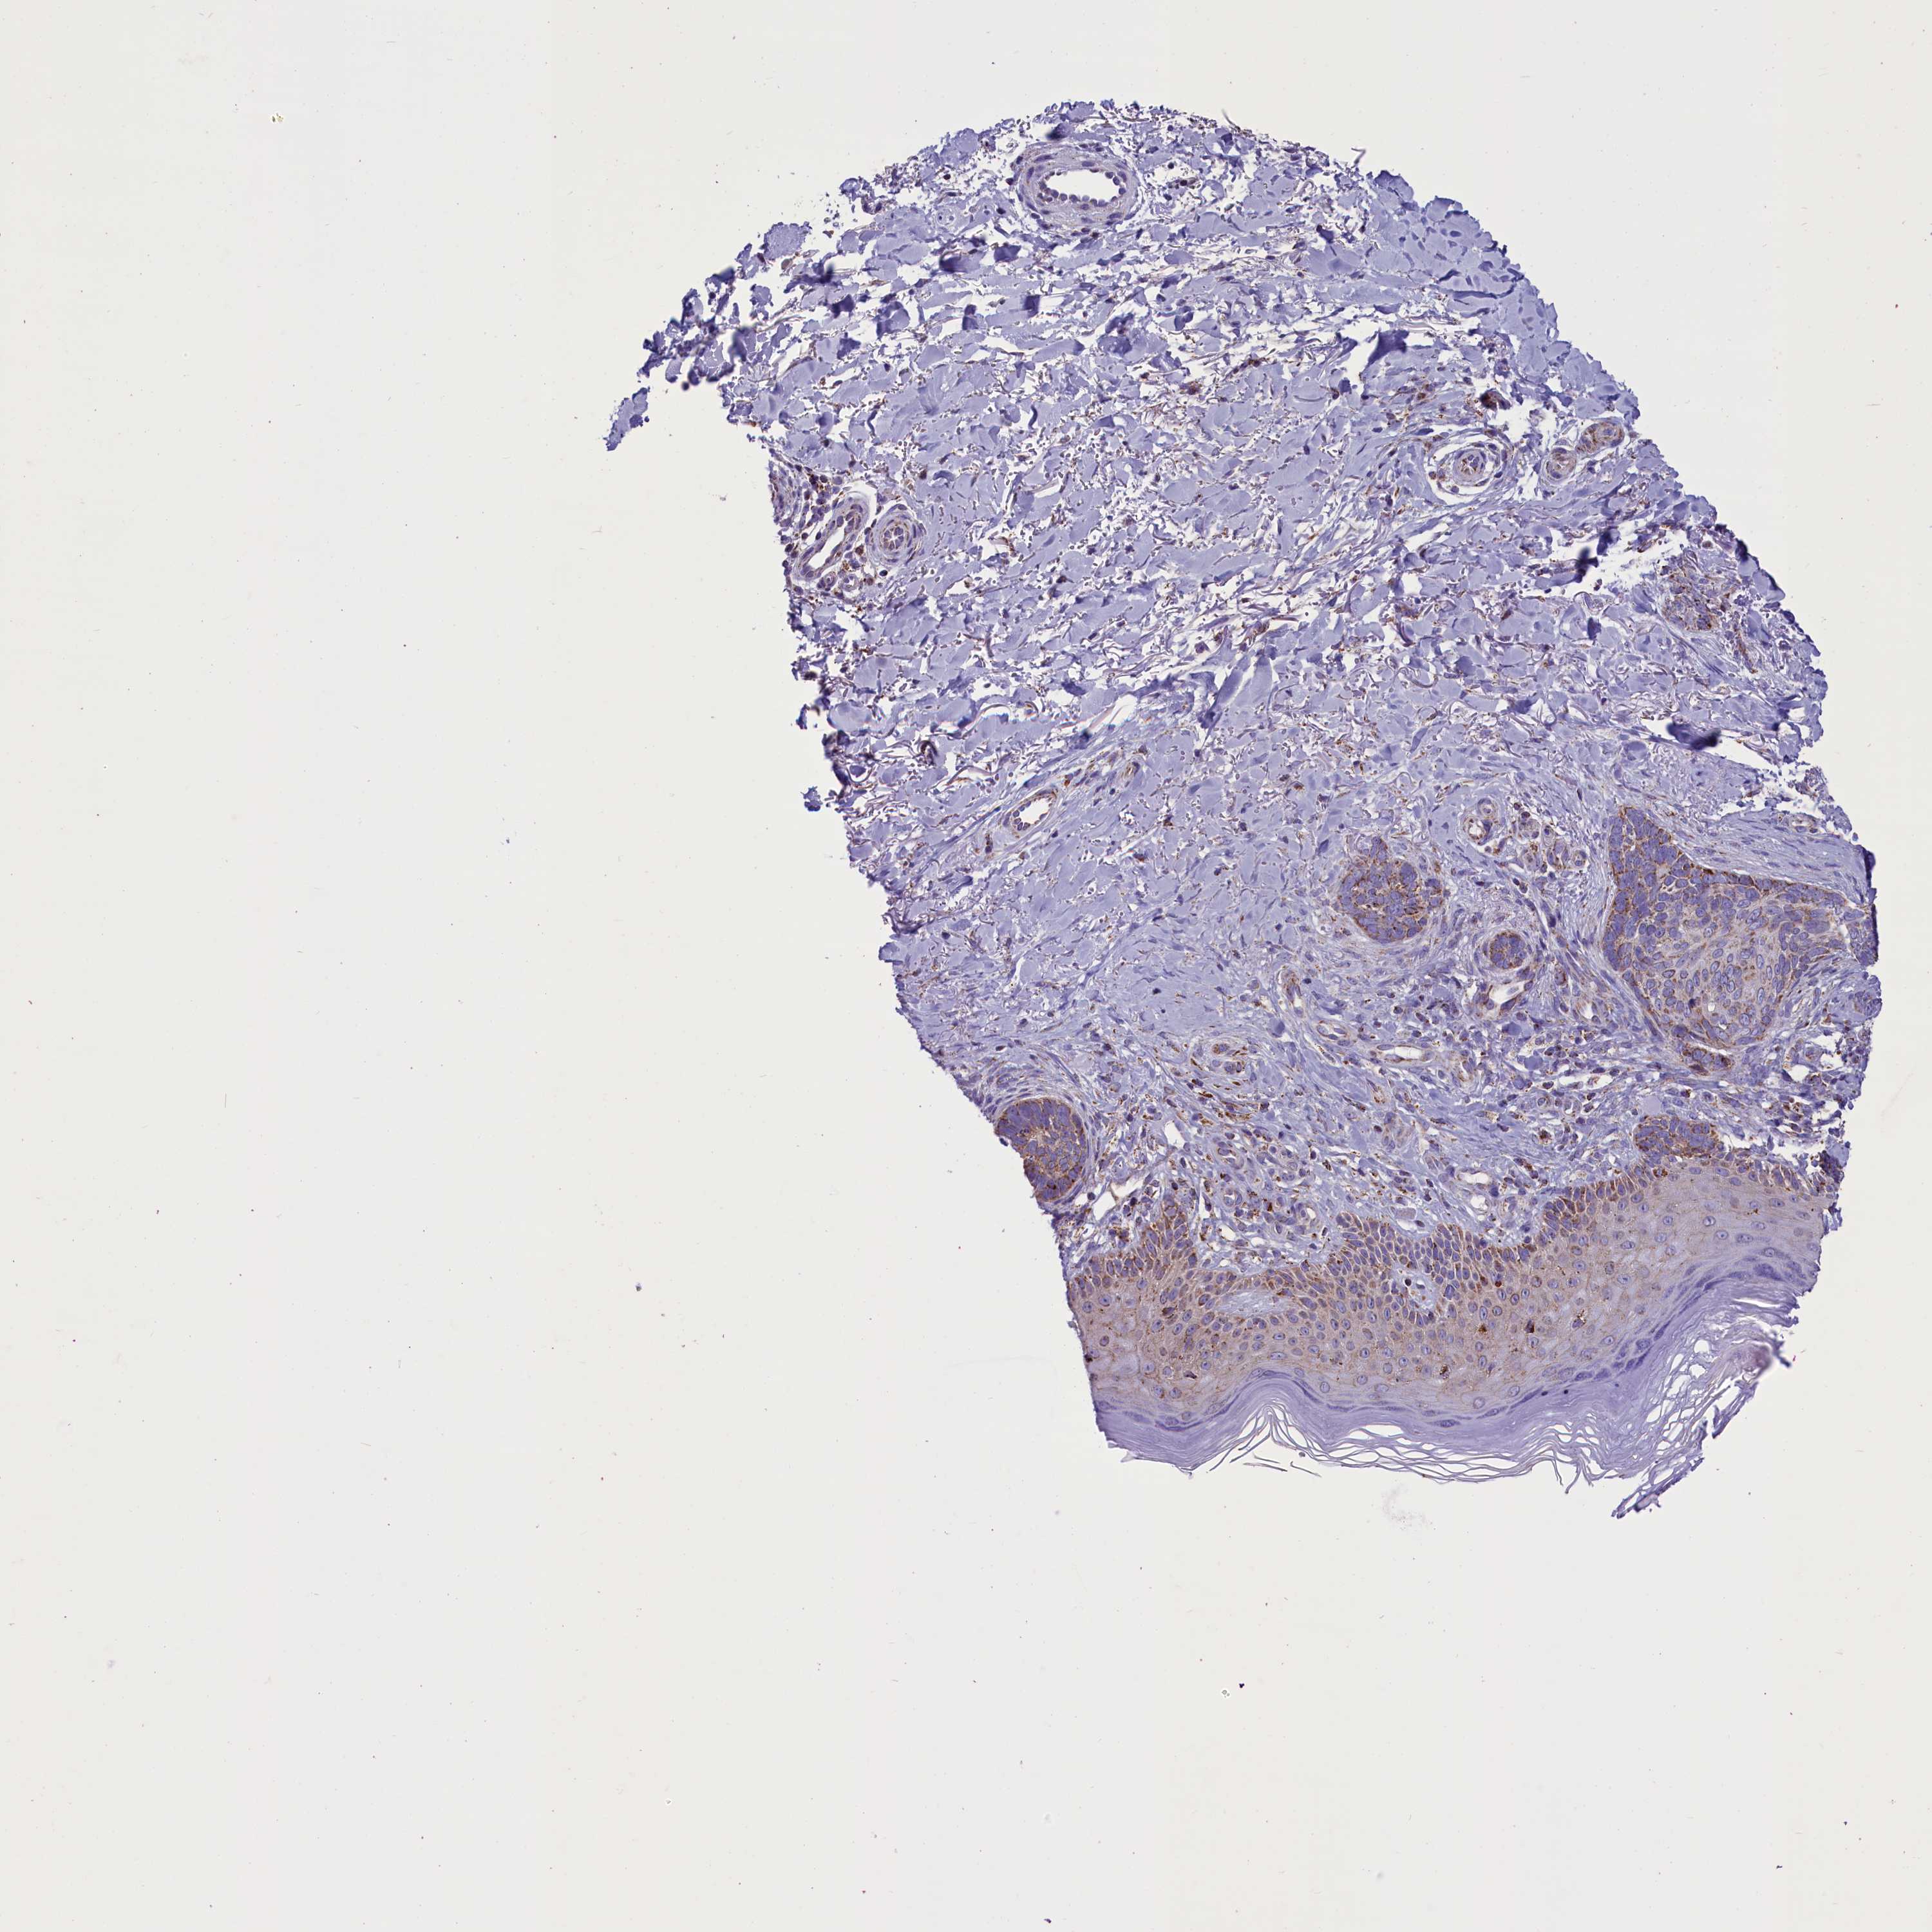

SKIN CANCER - Protein expressioni

A mouse-over function shows sample information and annotation data. Click on an image to view it in a full screen mode. Samples can be filtered based on level of antibody staining by selecting one or several of the following categories: high, medium, low and not detected. The assay and annotation is described here.

Antibody stainingi

Antibody staining in the annotated cell types in the current human tissue is reported as not detected, low, medium, or high, based on conventional immunohistochemistry profiling in selected tissues. This score is based on the combination of the staining intensity and fraction of stained cells.

Each image is clickable and will lead to virtual microscopy that enables deeper exploration of all samples and also displays staining intensity scores, fraction scores and subcellular localization as well as patient and tissue information for each sample.

Antibody HPA042507

Staining

High

Medium

Low

Not detected

Intensity

Strong

Moderate

Weak

Negative

Quantity

>75%

75%-25%

<25%

None

Location

Nuclear

Cytoplasmic/membranous

Cytoplasmic/membranous,nuclear

Squamous cell carcinoma, metastatic, NOS